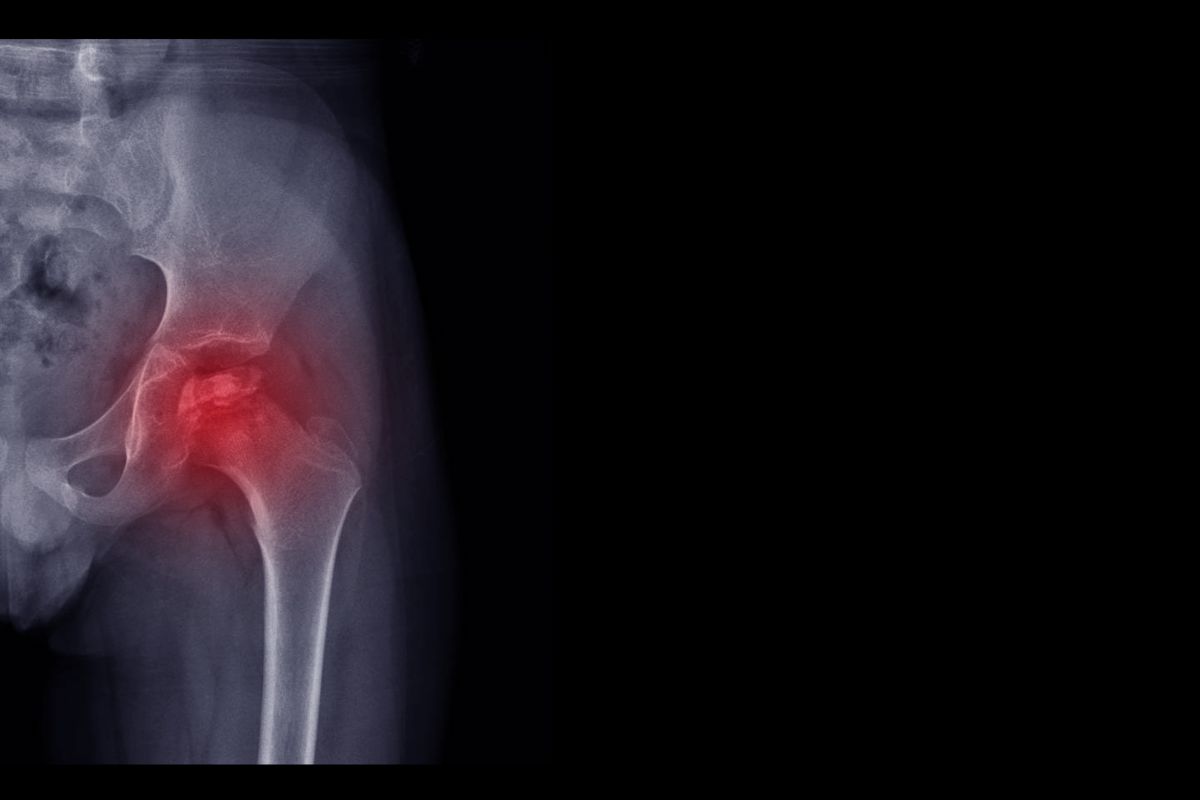

Malattia tipica dei bambini ma non solo, il morbo di Perthes colpisce l’articolazione dell’anca con conseguente zoppia, dolore o frattura. Scopriamone di più, incluse cause e rimedi!

Il morbo di Perthes è una malattia molto diffusa tra i bambini, ma anche qualche adulto ne è soggetto. Colpisce l’articolazione dell’anca, e in particolare la testa del femore, con gravi conseguenze. Tra esse risultano zoppia permanente, forte dolore, osteonecrosi (ovvero una morte prematura delle cellule ossee) e frattura. Ma scopriamo nel dettaglio di cosa si tratta, quali sono le cause e le soluzioni per curarla!

Il disturbo qui descritto viene anche chiamato morbo di Calvé-Legg_Perthes ed è molto diffuso tra i bambini. Ma anche tra gli adulti se ne sente parlare: come dimenticare il cronista di Temptation Island, Filippo Bisciglia? La malattia riguarda l’articolazione dell’anca in quanto si tratta di un’interruzione dell’afflusso sanguigno diretto alla testa del femore. Ciò comporta forti dolori e ripetuti rischi di frattura a causa dell’indebolimento e della morte prematura delle cellule ossee (detta ostenecrosi).

I sintomi di questo disturbo tipicamente infantile tendono a presentarsi in modo graduale. Includono zoppia, prima accennata e poi sempre più evidente, dolore in prossimità dell’anca, indebolimento con conseguente frattura ossea. Per ultimo, sui pazienti affetti è stato notato un accorciamento dell’arto inferiore della parte diagnosticata con il morbo.